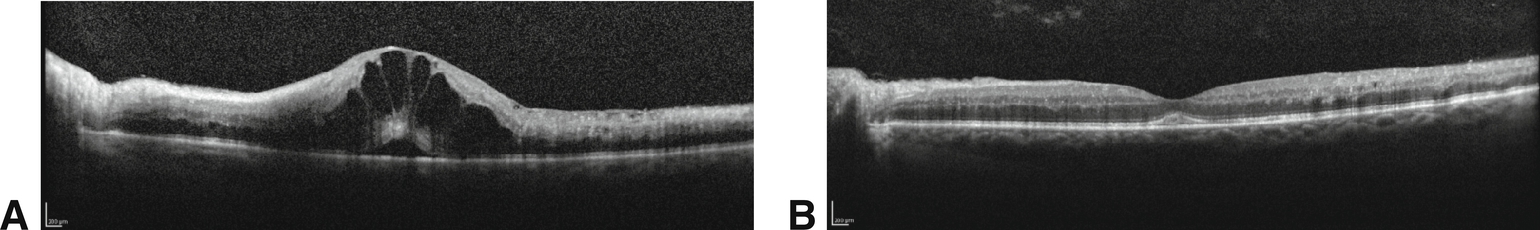

Figure 6-12

Œdème maculaire cystoïde (OMC) secondaire à une OVCR avant et après le traitement. A. OCT spectral-domain montrant un OMC sévère avec détachement fovéolaire chez un patient présentant une OVCR non ischémique. L'acuité visuelle était de 1/10. B. Un mois après une injection intravitréenne de bévacizumab, 1,25 mg, les lésions kystiques et le détachement fovéolaire ont disparu, et l'acuité visuelle est à 8/10.